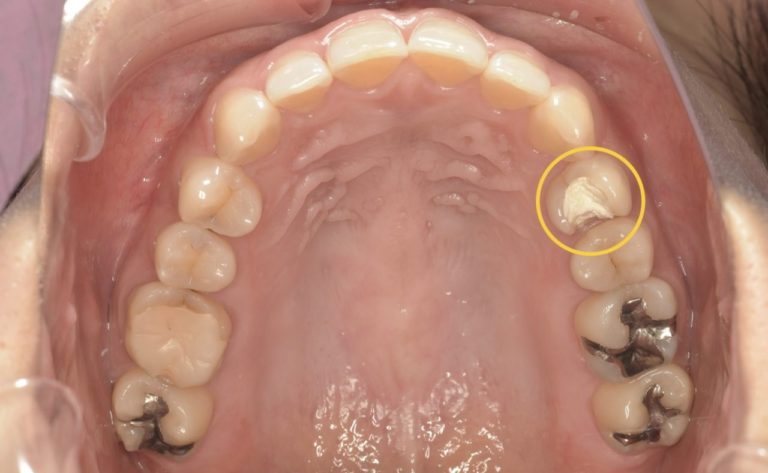

術前

| 年代/性別 | 40代/女性 |

|---|---|

| 症状 | 他院で2ヶ月間根管治療をしているが治らず、歯根端切除術を行う予定。 ただ、骨の吸収が大きく長く持たない可能性があり、抜歯になっても骨の吸収が大きく、インプラントはできない。 と診断された。 |

| 費用 | 初診診断料:¥16,500 感染根管治療:¥154,000 リトリートメント:¥44,000 MTAセメント::¥44,000 ファイバーコア:¥38,500 オールセラミックス:¥187,000 オールセラミックスインレー:¥99,000 歯髄温存療法:¥66,000 |

| 備考 | メリット:将来的に歯を保存出来る デメリット:歯科医師に高い技術が求められる |